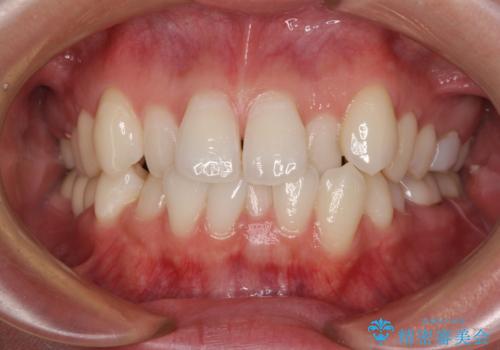

ワイヤー矯正後の後戻り 出っ歯を治したい マウスピース矯正